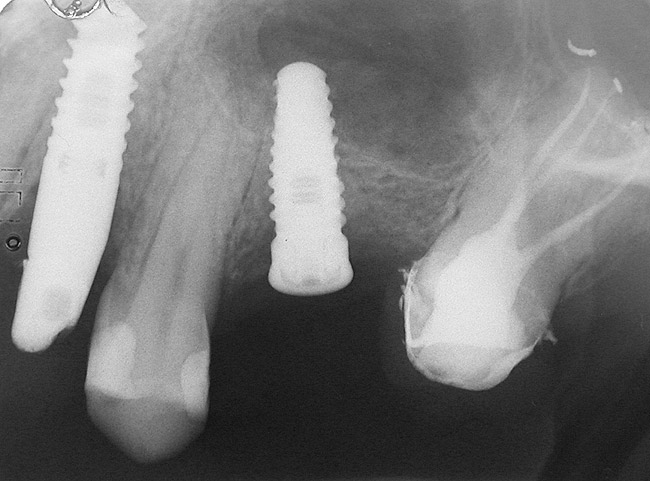

A 45-year-old female was referred for implant placement and prosthetic treatment in the area of tooth No. 24. The tooth had been extracted 4 years prior; the patient did not wear any denture thereafter. The radiograph revealed adequate bone height and a 5-mm to 6-mm ridge at the crest (Figure 2). It was decided to place a 11.5 mm in length, 3.75 mm in diameter Tapered Screw-Vent® implant (Zimmer Dental, www.zimmerdental.com) using the alveolar remodeling technique in the area of tooth No. 24.

Figure 2 Preoperative view of the area around tooth No. 24. On the left, a previously placed implant abutment

is visible.

Figure 4  Implant positioning; the radiograph taken 4 weeks after placement confirmed good primary stability.

Figure 2  Preoperative view of the area around tooth No. 24. On the left, a previously placed implant abutment is visible.